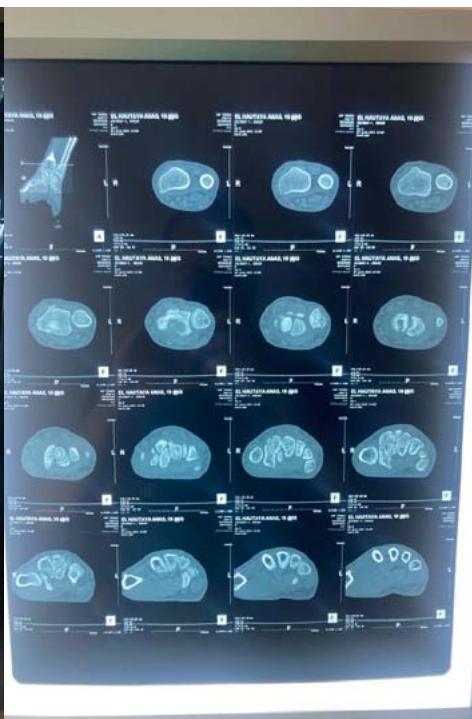

The patient underwent surgery via an anterior approach. Careful curettage of the cavity was performed after distraction of the fracture site. The bone defect was filled with autologous cancellous graft harvested from the lower metaphysis of the ipsilateral radius. Fracture stabilization was achieved with 2 pins (figure 3). The histopathological examination of the curettage specimen showed that the cyst wall was lined with flattened fibroblastic cells resembling synovial cells, without true epithelial appearance. There was no mucoid degeneration or myxoid transformation.

Figure 3: Postoperative radiograph after curettage, grafting, and stabilization with two pins.